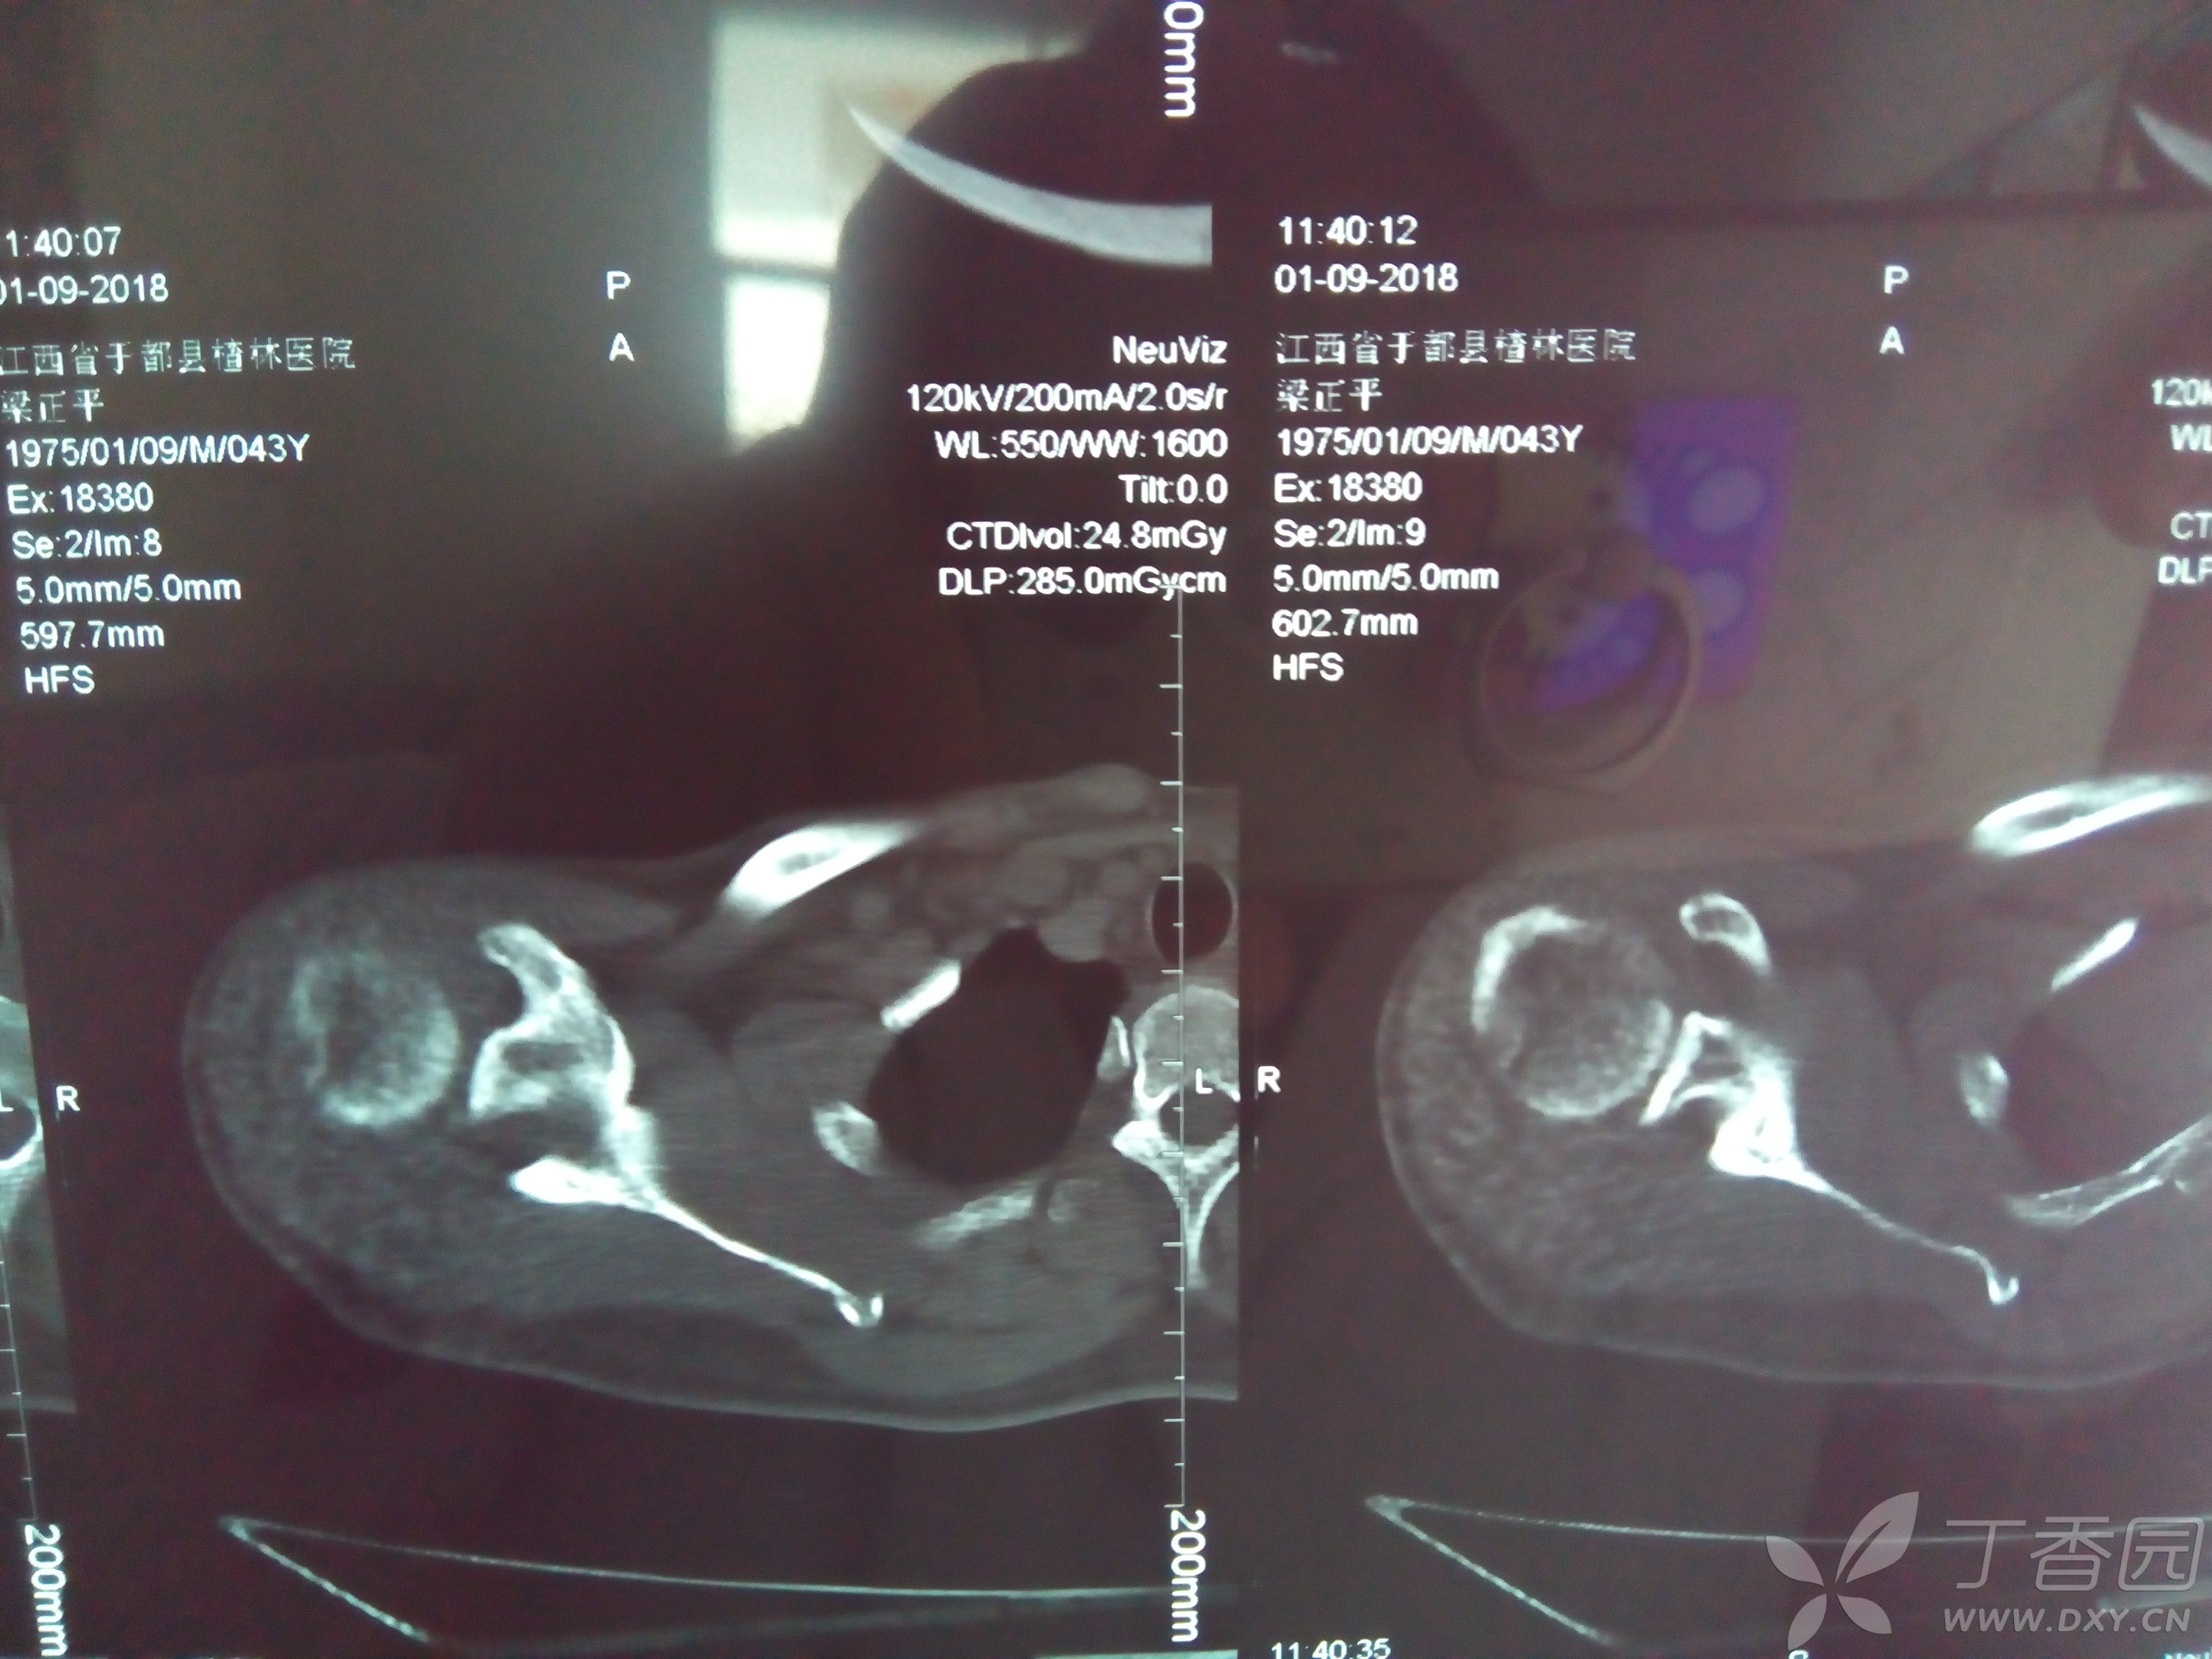

肩关节ct平扫图片,正常人肩膀ct图片

右肩关节ct三维重建

肩关节脱位有一骨块40天,请各位看看如何处理? [病例帖]

肩关节外伤平扫